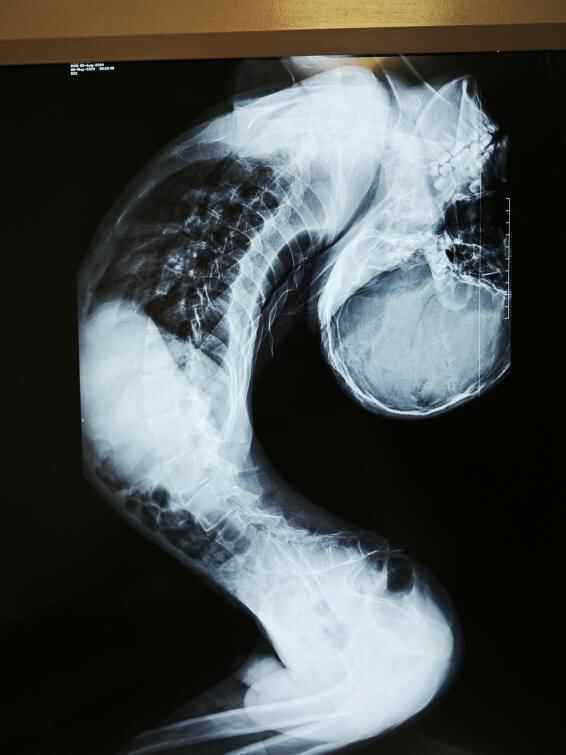

起初,他后仰的头还能被人轻轻扶正,后来脖子逐渐发硬;初三时,脖子折叠贴到后背;再往后,身体逐渐成了 “Z形” 畸形,头和脊柱之间仅有一只手厚度的间隙。

2023年5月,姜延琛因畸形导致呼吸困难,被诊断为脊柱反向折叠严重畸形,由基因突变引发的罕见性先天肌肉营养不良,在全世界都属首例。

这场手术的难度远超常规脊柱矫形,根源在于脊柱反向折叠的特殊性。与常见 “驼背”(正向折叠)不同,反向折叠患者的脊柱向反方向弯曲、拉长,胸腔薄如纸,肋骨无法膨胀,膈肌因胸腹腔高压难以下降。“从肚子上摸甚至能摸到主动脉,胸腔腹腔的整个前后径都很短,呼吸空间极度狭小,引起了呼吸衰竭。”梁益建说。

“就像在深井里操作,周围全是重要结构。”梁益建这样描述手术环境的严苛:脏器挤在狭长体腔内,腹腔高压使静脉血主要通过椎管内静脉丛回流,手术全程出血量较大,视野不清;脊髓被拉长变细,周围缠绕大量静脉丛,一旦损伤便意味着瘫痪;姜延琛既往手术导致颈椎解剖结构破坏,颈椎前后截断操作需精准避开椎动脉,毫米级偏差都可能致命。团队创新采用“反向截骨”方案,将拉长的脊柱矫正成类似“驼背”的状态以创造空间。

从2024年12月4日的反向截骨矫形手术,到2025年2月19日的颈椎截骨矫形翻修手术,再到2025年4月17日的髋关节松解手术,直至2025年6月25日的胸椎段矫形手术,梁益建主任带领团队先后为姜延琛开展4次手术,矫正约170度,这也标志着成都京东方医院完成了世界首例反向折叠人矫正手术。